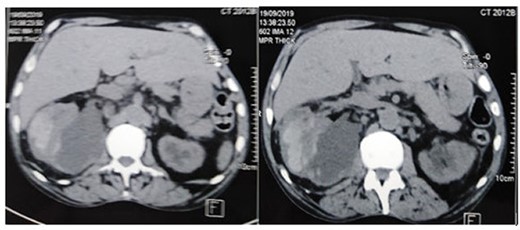

A 67-year-old patient, smoker, diabetic on insulin, who was initially admitted to hospital for the management of a right distal ureteral stone of 1 cm. He had a right ureteroscopy with the insertion of a DJ ureteral stent. The post-operative course was uneventful. After 1 month, the patient consulted us for deterioration of the general condition associated with right lumbar pain. Clinical examination showed poor general condition, pallor, hypotension and tachycardia. The urological examination showed a contracture of the right lumbar fossa. Biological analysis showed microcytic hypochromic anemia, (hemoglobin: 4.8 g/dl), thrombocytopenia and renal failure with high C-reactive protein (CRP) levels (Table 1). The patient was admitted to the intensive care unit. After transfusion and stabilization of the hemodynamic state, a radiological exploration by computed tomography (CT) was made. The CT scan revealed a huge subcapsular hematoma (12 × 14 × 10 cm) of the right kidney (Fig. 1). The proximal end of the DJ stent was in the renal pelvis. Despite resuscitation and transfusion, the patient remains hypotensive and severely tachycardic. an open right nephrectomy was performed as an emergency. The patient had an uneventful recovery and was discharged on the seventh post-operative day. Histological examination did not show a malignant lesion. After 24 months of clinical and radiological controls, there were no functional complaints or signs of lithiasis recurrence. Renal function was normal.

The CT scan showed a huge subcapsular hematoma (12 × 14 × 10 cm) of the right kidney.